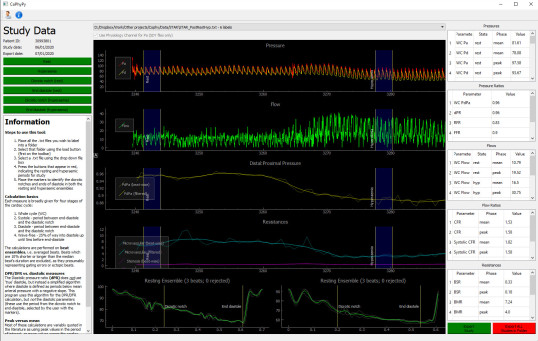

CoPhy - Coronary physiology in Python - LINK

CoPhy free to use coronary physiology package that can calculate the common coronary physiology parameters including FFR, iFR, DFR, RFR, CFR, BSR, BMR and HMR. Parameters are given for full cycle,

diastole, systole and the wave-free period.